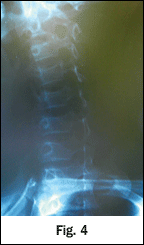

On the first spinal manipulation, he experienced a sudden increase in cervical tone of the left SCM, and reported a sudden decrease in pain with motion. No new pain with radiation into or down his left arm or with numbness in his fingers developed, nor did he develop any weakness in his left hand. He was seen subsequently for 12 conservative measures; 50 percent of the time he received spinal adjustments and he did improve. There was an indication of a relative contraindication to CSMT based upon the disease process. He previously had undergone radiological imaging, which revealed an antalgic list (Fig. 1), sigmoid-type curve and loss in cervical lordosis and a slight segmental flexion and anteriolisthesis (Fig. 2), consistent to a whiplash or CAD injury presentation. Cervical oblique (Fig. 3-4) failed to demonstrate any cervical stenosis. Open-mouth odontoid or dens (Fig. 5) failed to demonstrate any developmental deficiencies of the cervical spine, i.e., agenesis or odontoid hypoplasia. A low-force technique mode was chosen and discussed with the family. At the conclusion of care, the patient had experienced a complete recovery of his acute pain state.